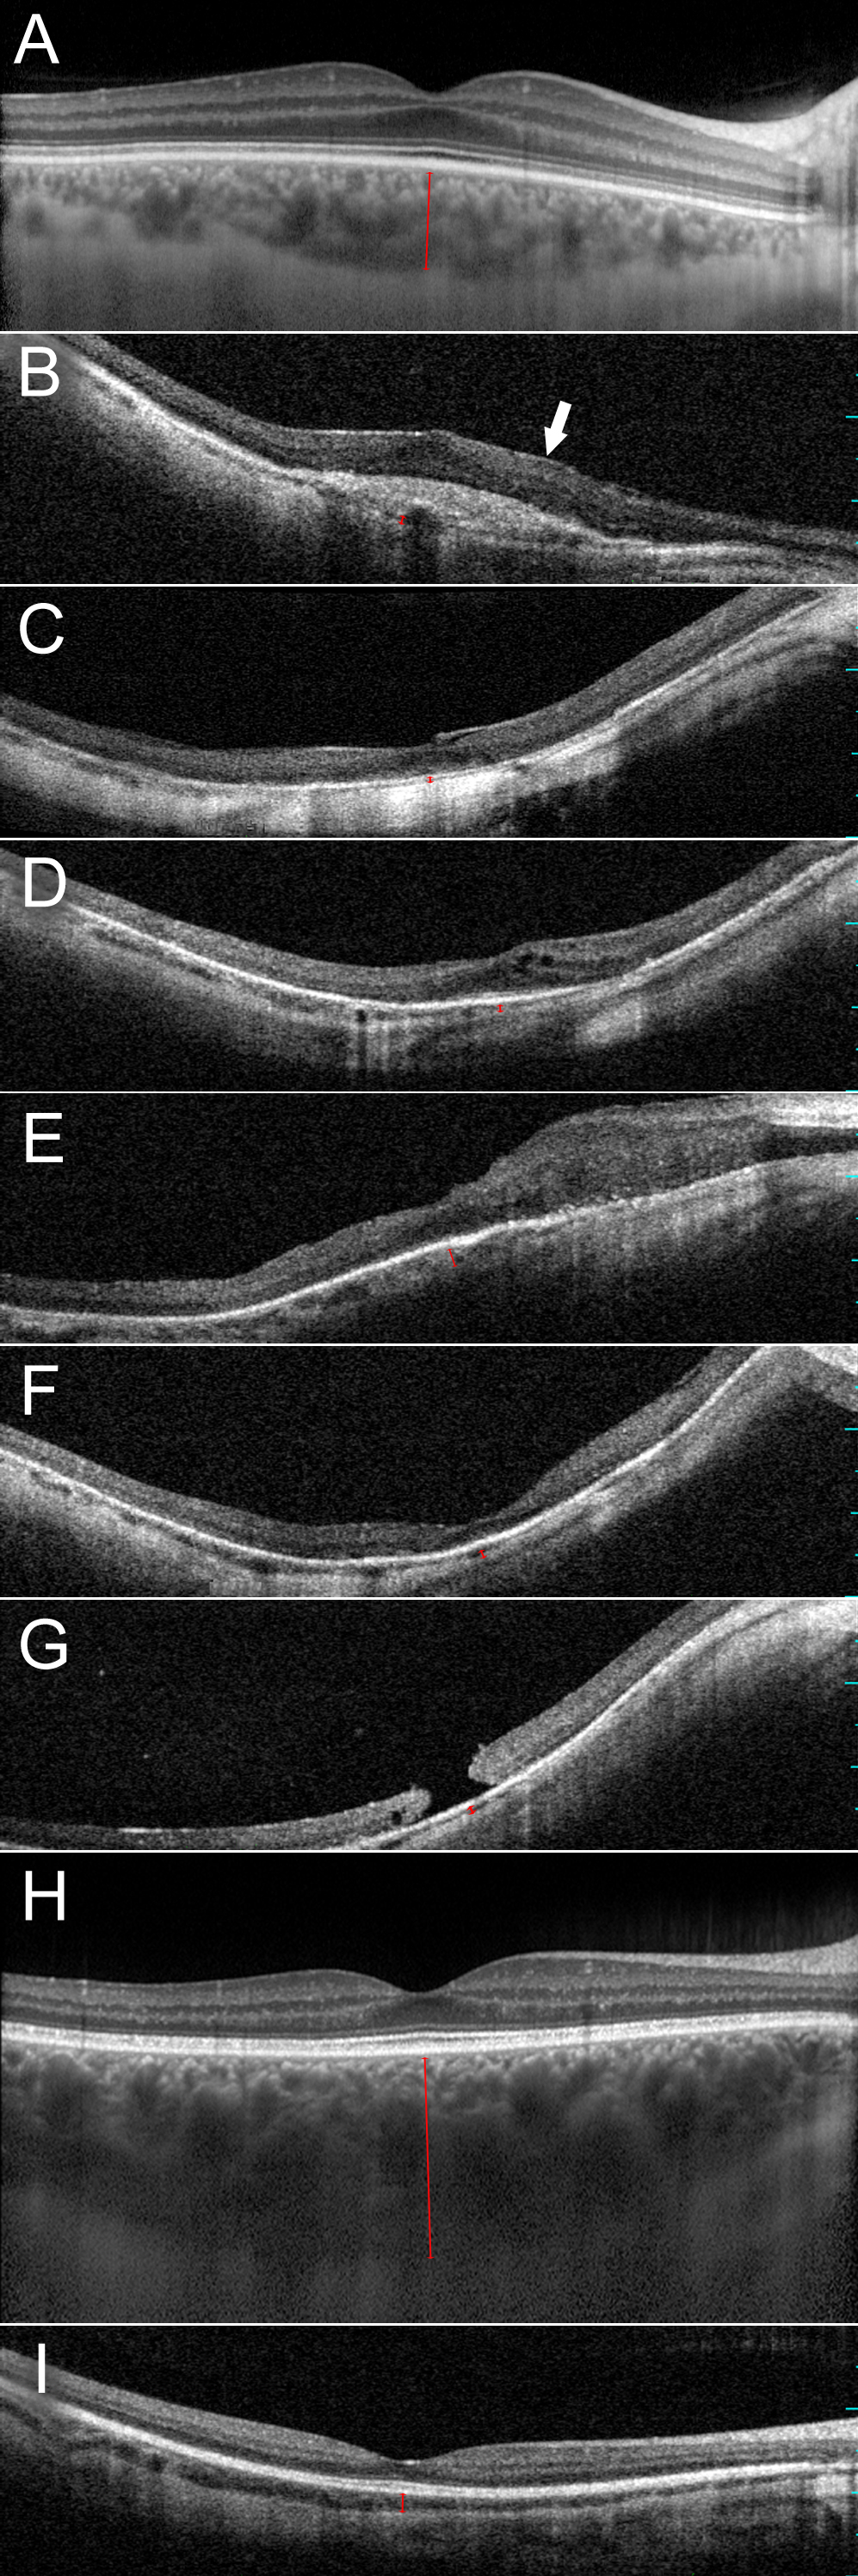

Figure 3. Horizontal optical coherence tomography images cross sectioning the fovea in the right eyes of affected men and women who

carry a c.2543del mutation in RPGR ORF15. Choroidal thickness is indicated with a red bar. A: Normal retinal architecture in a 40-year-old control individual (enhanced depth imaging). B: Chorioretinal thinning, missing foveal depression, scar formation, and epiretinal membrane (arrow) in female III:1 at the

age of 64 years. C: Chorioretinal thinning, missing foveal depression, and vitreomacular traction associated with foveal elevation in female

III:4 at the age of 54 years. D: Chorioretinal thinning, myopic foveoschisis, and posterior staphyloma in female III:9 at the age of 50 years. E: Chorioretinal thinning and focal retinal thickening in male IV:1 at the age of 42 years. F: Chorioretinal thinning and myopic posterior staphyloma in male IV:2 at the age of 38 years. G: Chorioretinal thinning, macular hole, and myopic posterior staphyloma in male IV:3 at the age of 30 years. H: Normal retinal and choroidal architecture in female IV:4 at the age of 32 years (enhanced depth imaging). I: Choroidal thinning and normal retinal architecture in male IV:6 at the age of 19 years.